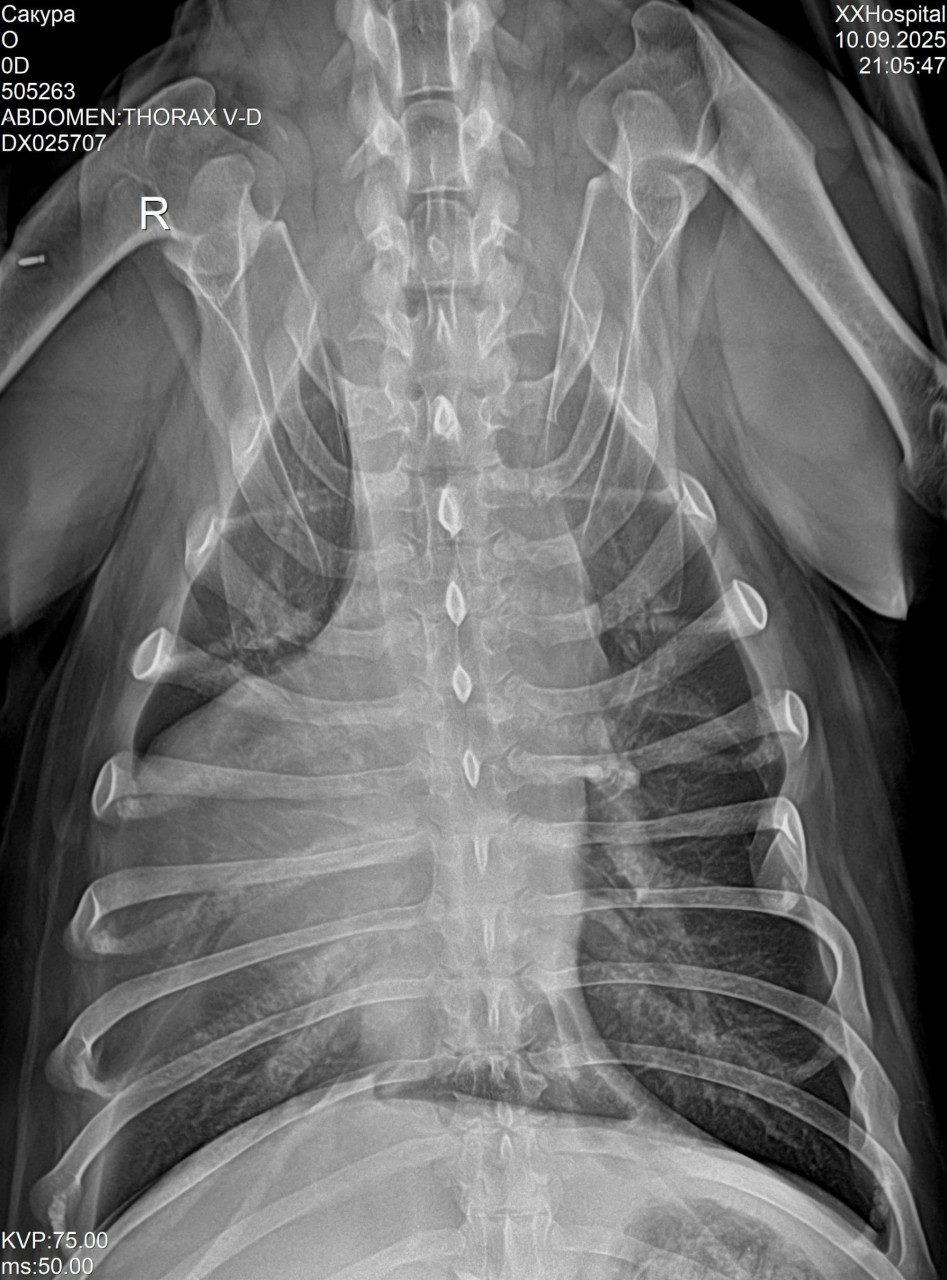

Добрый день, подскажите пожалуйста что по снимку у собачки, напугали каким то заворотом легкого

Здравствуйте. По снимкам видна неоднородность в лёгких, но поставить диагноз «заворот доли лёгкого» только по рентгену нельзя т.к требуется клиническое обследование и  КТ. Обязательно покажите результаты ветеринарному пульмонологу.

Была пневмония, скажите пожалуйста очень серьезное что то по снимку или это вариант нормы после пневмонии

И еще что то с сердце, геометрия нарушена, вы это тоже видите на снимке?

После пневмонии на рентгене могут сохраняться остаточные изменения и это вариант нормы, но для точной оценки нужно сравнение с предыдущими снимками. Что касается сердца, то по рентгену его форму и размеры можно лишь предположить, окончательно оценить геометрию можно только на ЭКГ и ЭхоКГ.